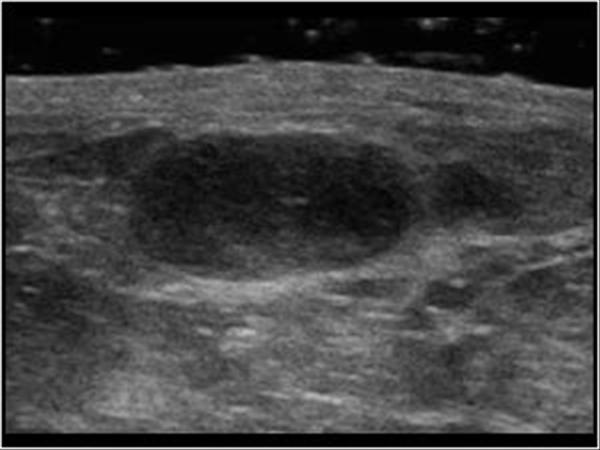

Hoại tử mỡ tuyến vú

» Thông tin: Nữ giới – 54 tuổi.

» Lâm sàng: Khối tuyến vú / Sau phẫu thuật u vú.